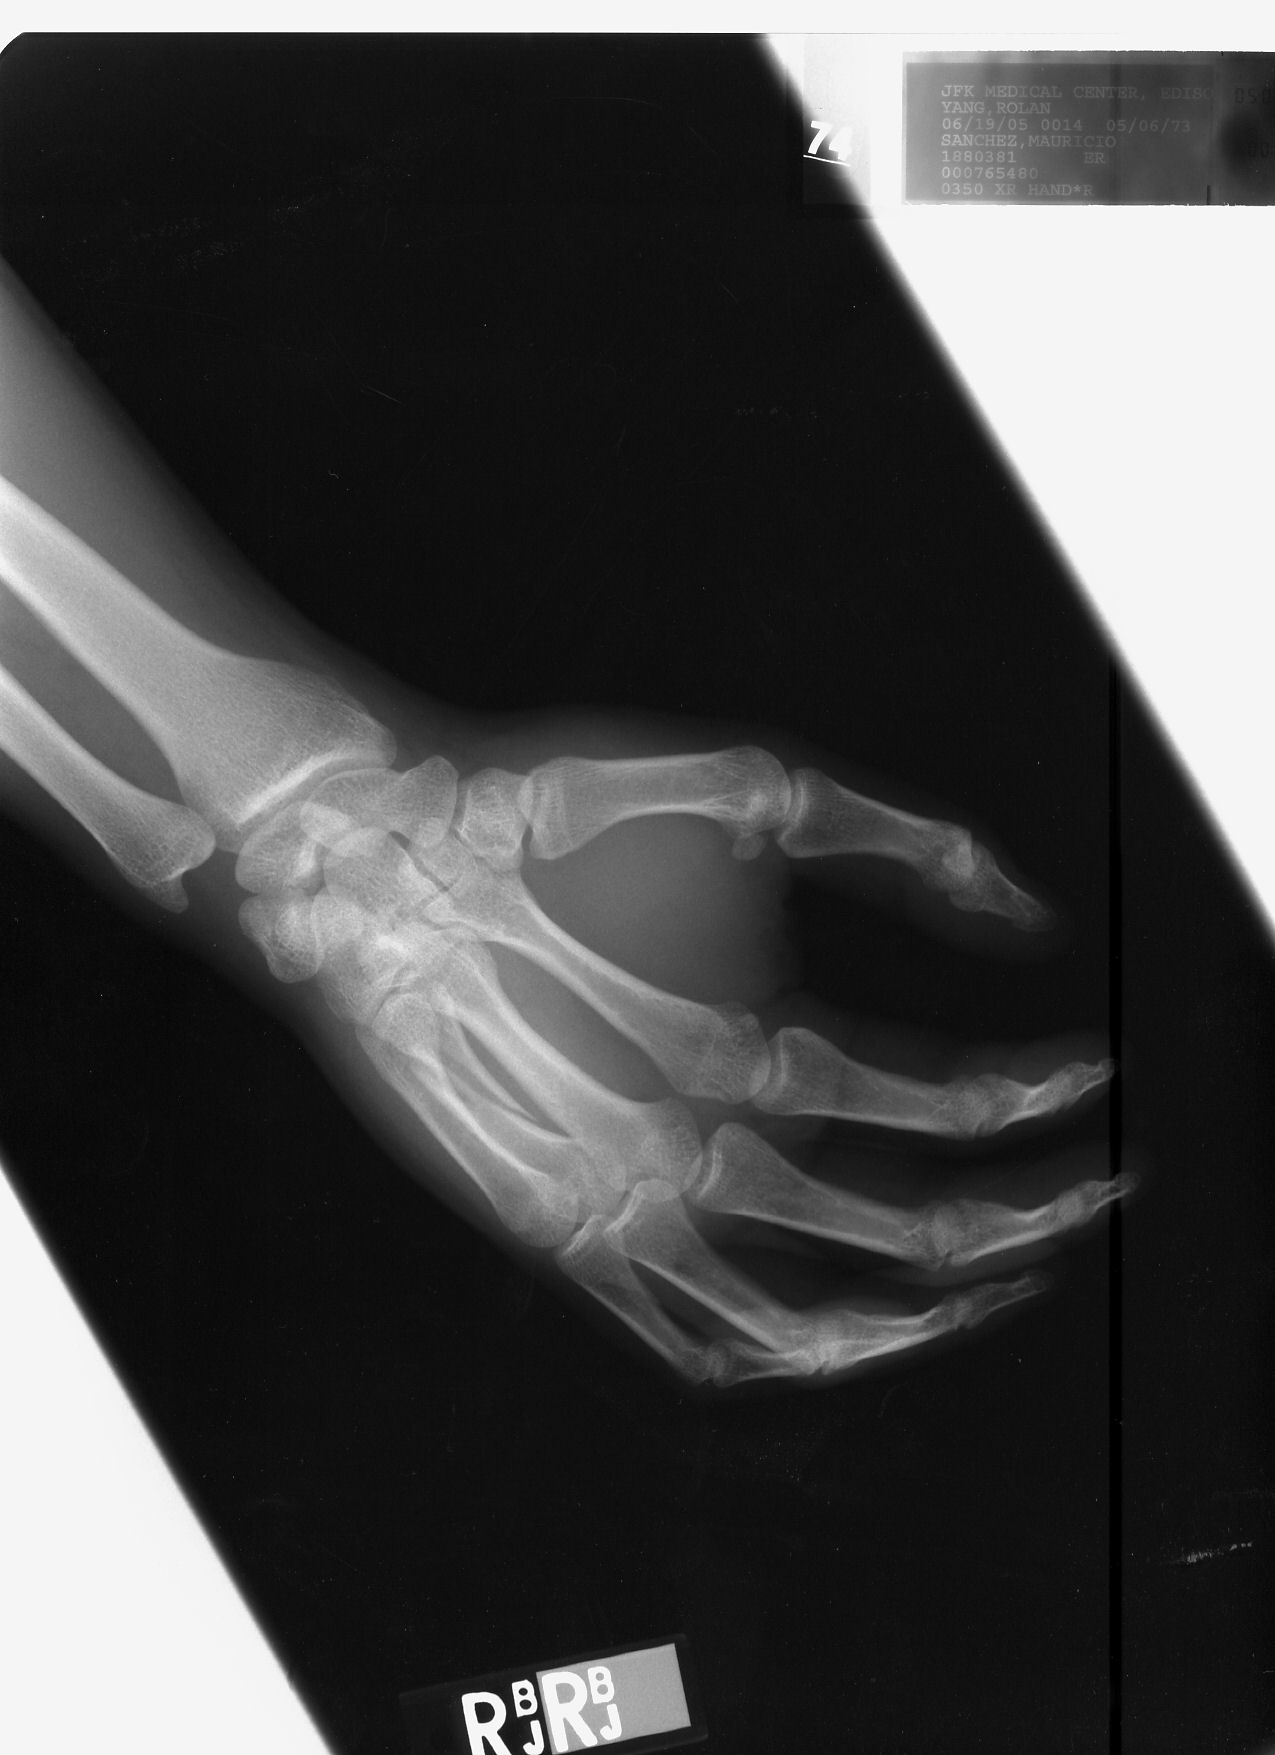

Longitudal fracture fourth metacarpal right hand

6/19/2005 See 4th (ring) finger.